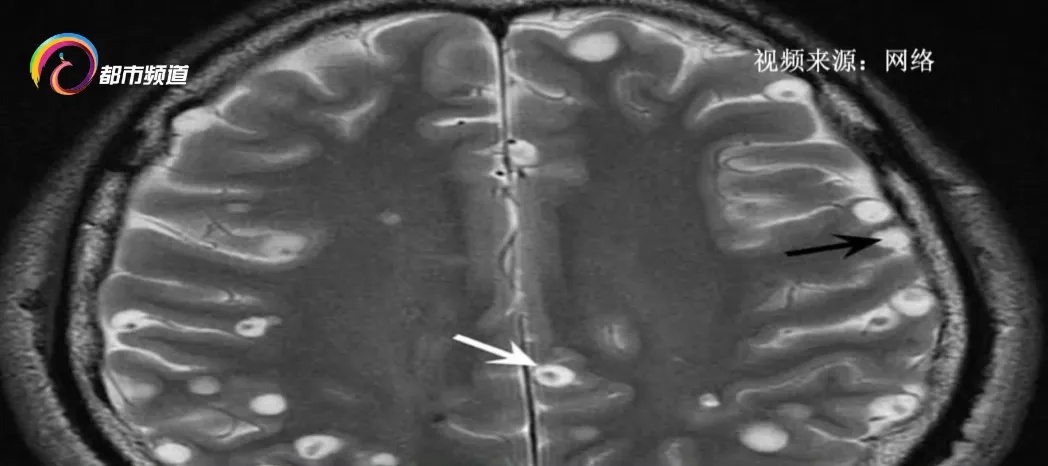

昆明市第三人民医院感染性疾病首席专家 黄瑛:“有一个病人,他是头痛来医院,检查时看到脑子里有一圈一圈的东西。一开始,我们说是不是结核性脑膜炎,再进一步看就是脑囊虫病。”

昆明市第三人民医院感染性疾病首席专家 黄瑛:“猪带绦虫的囊尾蚴可能会跑到脑子里,形成脑囊虫病。脑囊虫病就很厉害了,特别是囊虫在脑里死掉后,会释放炎症因子,和身体免疫发生反应,引起局部的脑水肿。水肿后,改变大脑的生理结构,非常危险,像癫痫的发作,有的人可能会有生命危险。”